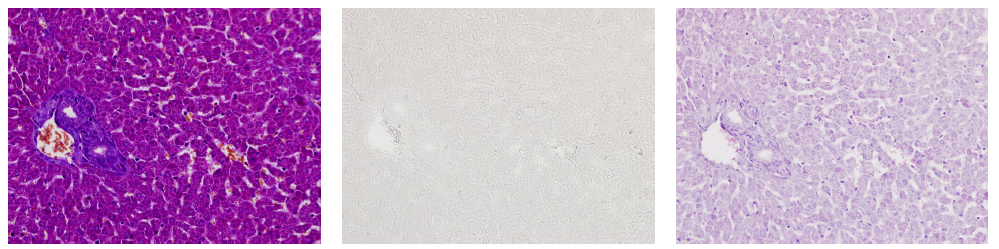

使用小鼠肝臟標本進行MT染色時

使用deColorizing Solution 1和2進行脫色

左至右:MT染色→脫色→HE染色

(數據提供:麻布大學小澤秋沙先生、坂上元榮先生)